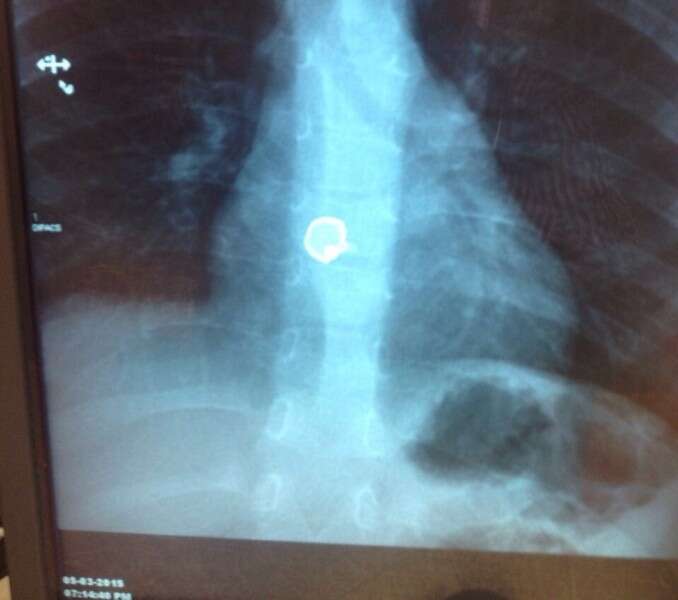

ההורים מיהרו לפנות למרפאת "טרם" שם נבדק הילד, וצילום רנטגן הראה כי הפעמון "תקוע" בוושט והוא הופנה למיון ילדים בשערי צדק. "מדובר במקרה נדיר", אומר פרופ' דן טרנר, מנהל גסטרו ילדים בשערי צדק. "הפעמון נתפש ברירית הוושט, רירית בצקתית מאד, ולא התקדם לעבר הקיבה. היה הכרח לחלץ אותו שכן היה חשש לפרפורציה – נקב במעי שיגרום הגוף הזר".

צילום הרנטגן של הילד לאחר בליעת הכפתור